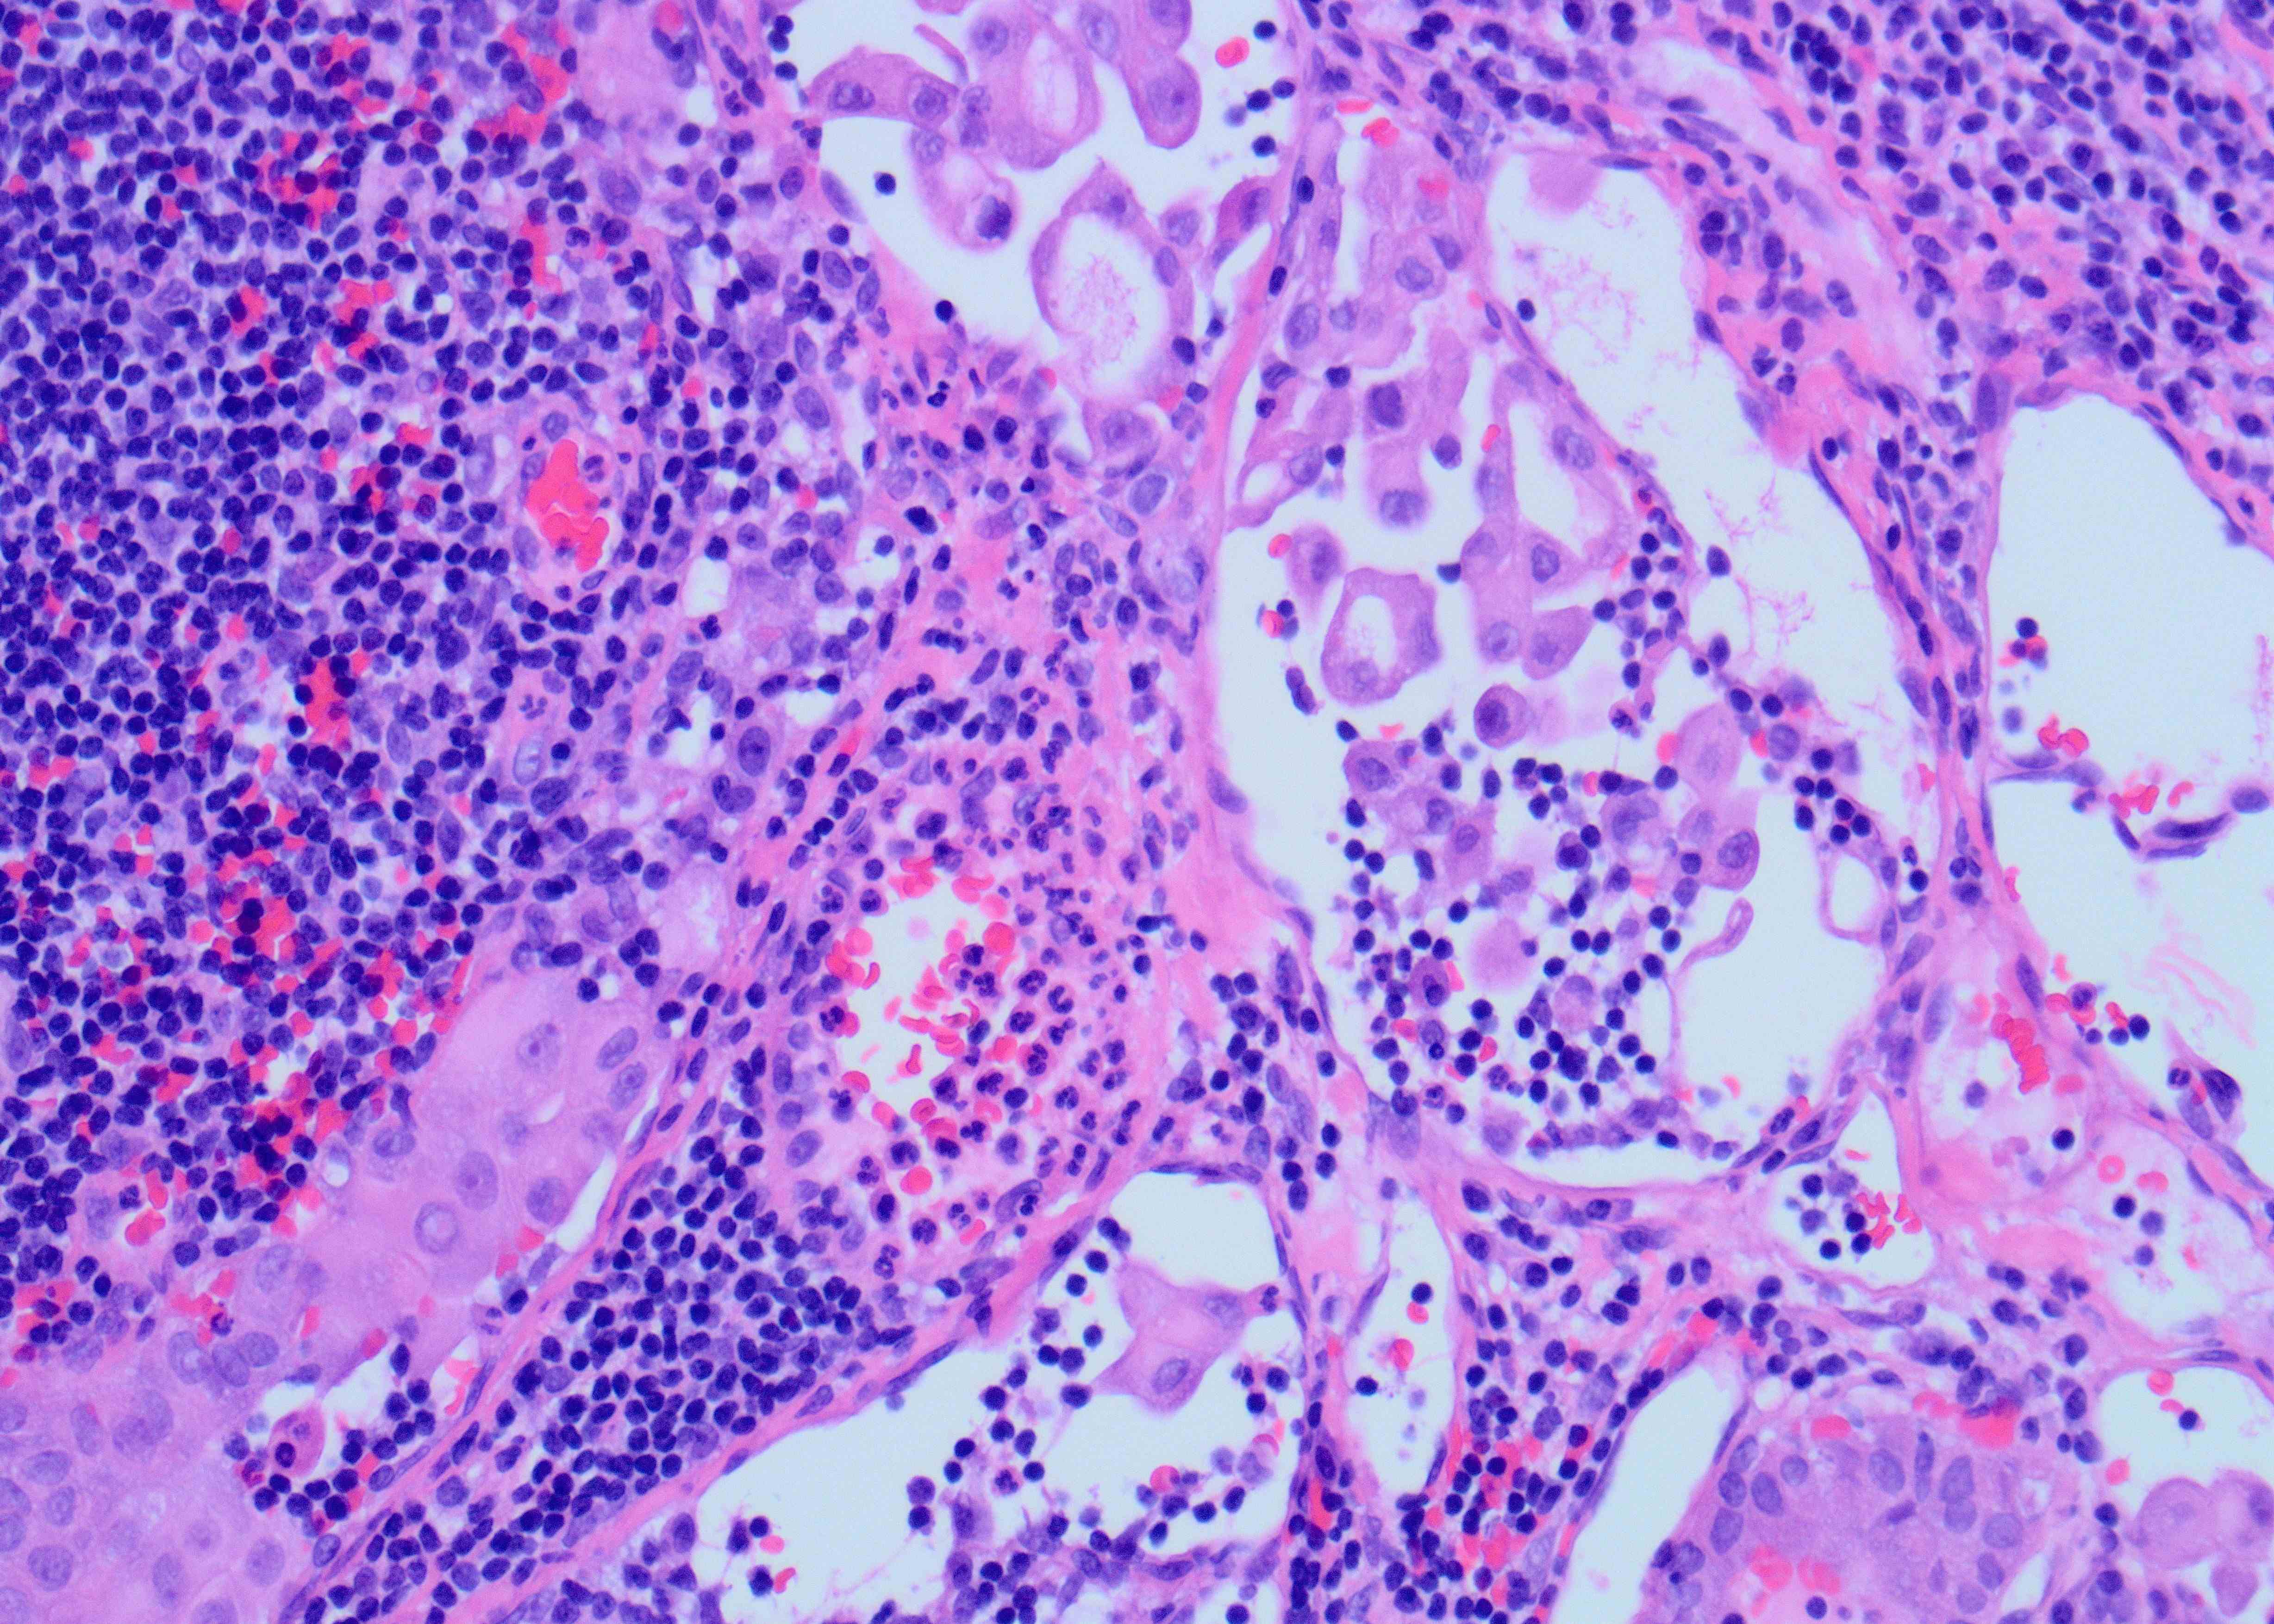

A 45-year old man with a history of PTC, tall cell variant (PT3b N1a M0), s/p total thyroidectomy, central neck lymph node excision and radioactive iodine therapy, presents with new neck mass. Figures a & b show FNA of the mass.

Although the specimen source was described as a neck mass, the presence of scattered lymphocytes in the back ground is suggestive of a lymph node aspirate. In addition, there are scattered clusters of large epithelioid cells but with relatively low nuclear to cytoplasmic ratio due to moderate amount of cytoplasm showing tapered cytoplasmic tails (Figure A). The high power shows a syncytial aggregate of atypical cells (Figure B). These cells have moderately abundant amount of granular cytoplasm with distinct margins. Occasional cells have tall cell morphology, evident predominantly along the periphery of the cluster as well as a single cell with soap bubble like intranuclear pseudoinclusion (arrow). The cytomorphology is identical to the metastatic cells present in the previously excised cervical lymph node (Figure C). All these features favor tall cell variant of papillary thyroid carcinoma (PTC), metastatic possibly to a cervical lymph node. Histopathologic feature of primary PTC, tall cell variant, is shown in Figure D.

PTC is the most common malignancy of the thyroid gland and has overall a favorable prognosis, with few exceptions like PTC, tall cell variant. This variant of PTC is often associated with more aggressive behavior with a higher risk of recurrence than classic PTC. Therefore, a preoperative diagnosis of tall cell variant or even noting the tall cell features on FNA may help in triaging for appropriate patient management. The most helpful cytologic diagnostic features include increased numbers of tall tumor cells arranged as single cells and at the periphery of cellular groups containing granular cytoplasm and distinct cell borders, cytoplasmic tails, and cytoplasmic cuffs (peripheral rimming of cytoplasm in cellular groups). Intranuclear “soap-bubble” pseudoinclusion is not readily identifiable but when present is specific for tall cell variant/ changes.